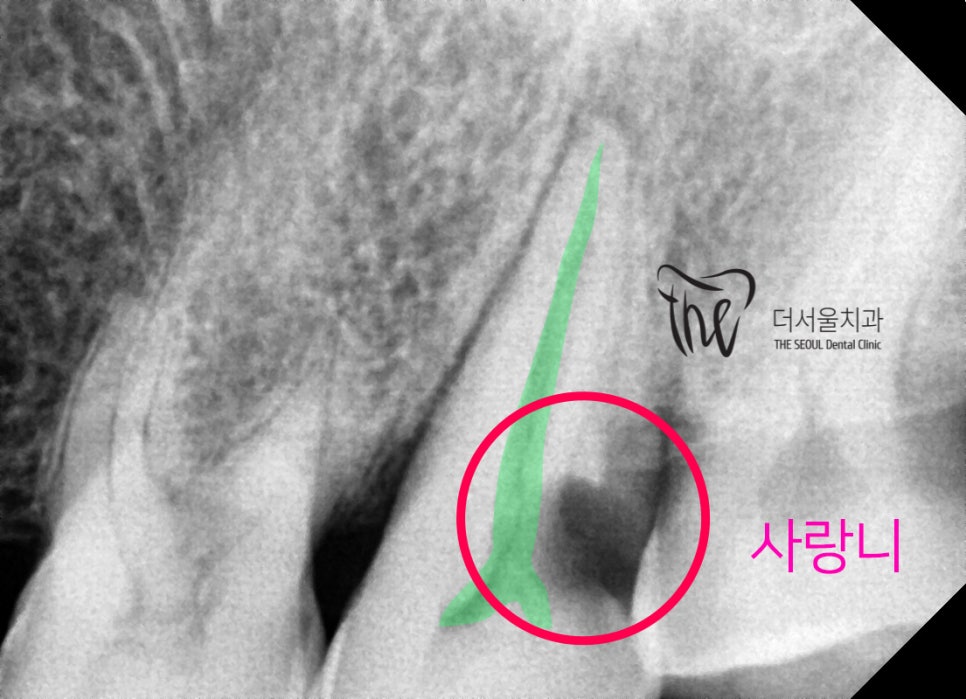

해상도 높은 방사선 사진을 찍어서 보면,

사랑니와 사이에 Proximal caries 가

발생이 되어있는 것을 볼 수 있었습니다.

사이 충치.. 라 부르죠?

영어로는 Proximal caires 라 부릅니다.

육안검진에서는 쉽게 발견을 할 수 없기

때문에 이렇게 엑스레이를 찍어야

판독을 할 수 있습니다.